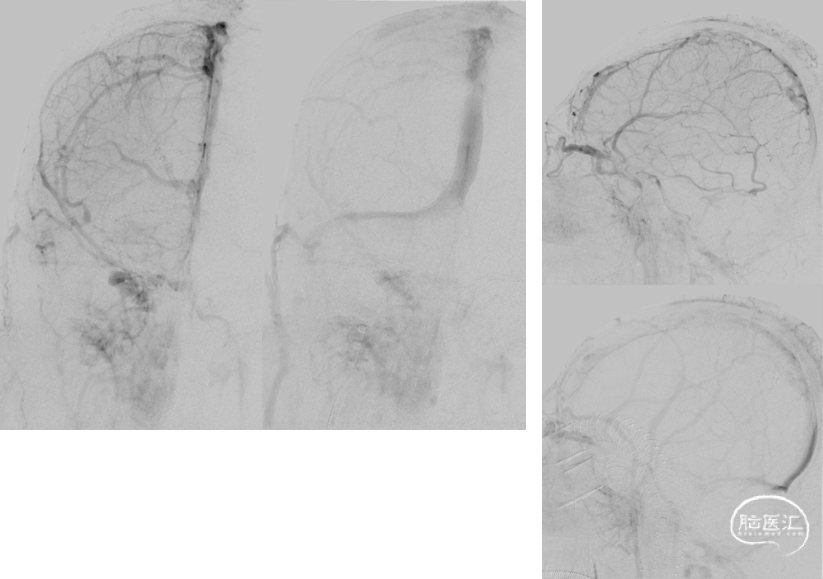

术前DSA

在泥鳅导丝导引下将8FGuiding内衬多功能导管,置于上矢状窦

以8FGuiding反复负压抽吸,可见抽出大量暗红色血栓

手推造影,静脉回流缓慢,上矢状窦仍显影欠佳

将EV3 6.0mm保护伞及6*30mm球囊置于上矢状窦,释放保护伞,以保护伞及球囊反复抽拉捣碎上矢状窦、右侧横窦及乙状窦血栓

以10atm压力扩张上矢状窦后反复抽拉

以10atm压力扩张右侧横窦后反复抽拉

复查造影上矢状窦显影好转,静脉回流较前改善,右侧横窦及乙状窦仍显影欠佳

再次将导引导管置于右侧横窦及乙状窦进行负压抽吸,可见抽出暗红色血栓,手推造影示:静脉回流较前明显改善,右侧横窦及乙状窦仍显影欠佳